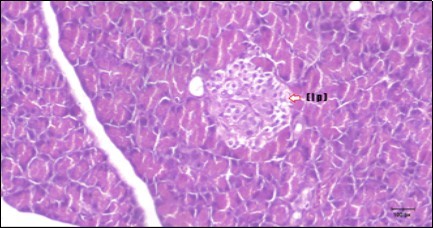

Pancreas Histopathological Observations

Histological examination of pancreas of the control rats showed normal sized islets of pancreas (Ip) compared to the diabetic rats which showed markedly atrophic islets of pancreas (I.p.) (Figure 8 and Figure 9). Pancreas of in groups (3) and (4) rats showed mild atrophic islets of pancreas (I.p.) with inflammatory cellular infiltrate (Figure 10 and Figure 11). The pancreas of rats in group (5) showed nearly normal islets of pancreas (I.p.) with few inflammatory cellular infiltrate (I.c.) (Figure 12).

Figure 10.Photomicrogragh of pancreas section of treated rat with Fenugreek showing less improved islets of Langerhans with more cells (star). (H&E) (40X).

Figure 11.Photomicrogragh of pancreas section of treated rat with Glimepiride showing mildly improved of isled of Langerhans with large number of cells (dashed-arrow). (H&E) (40X).

Figure 12.Photomicrogragh of pancreas section of treated rat with both Fenugreek and Glimepiride showing nearly normal islets of Langerhans with spindle (arrow) & polygonal cells (dashed- arrow). (H&E) (40x).

Histopathological observation in diabetic control showed degenerative changes in both endocrine and exocrine pancreases. A probable explanation may be related to oxidative stress resulting from hyperglycemia which decreases the antioxidants levels and increases ROS 33 and the activities of antioxidant enzyme were altered in diabetic rats. These effects further exacerbate the development and progression of diabetes complications and these may represent the causes of degeneration revealed in histological sections. Fenugreek improved blood glucose levels and insulin, lowered pancreatic islet and β-cells damage which may be attributed to its immune modulatory activity and insulin stimulation action along with its antioxidant potential 32. Glimepiride caused restoration of morphology of beta cell of diabetic and it increased percentage of beta cells 34. This protective effect could be attributed to the antioxidant properties of Glimepiride. Combination therapy improves the protective effect of both therapies alone.